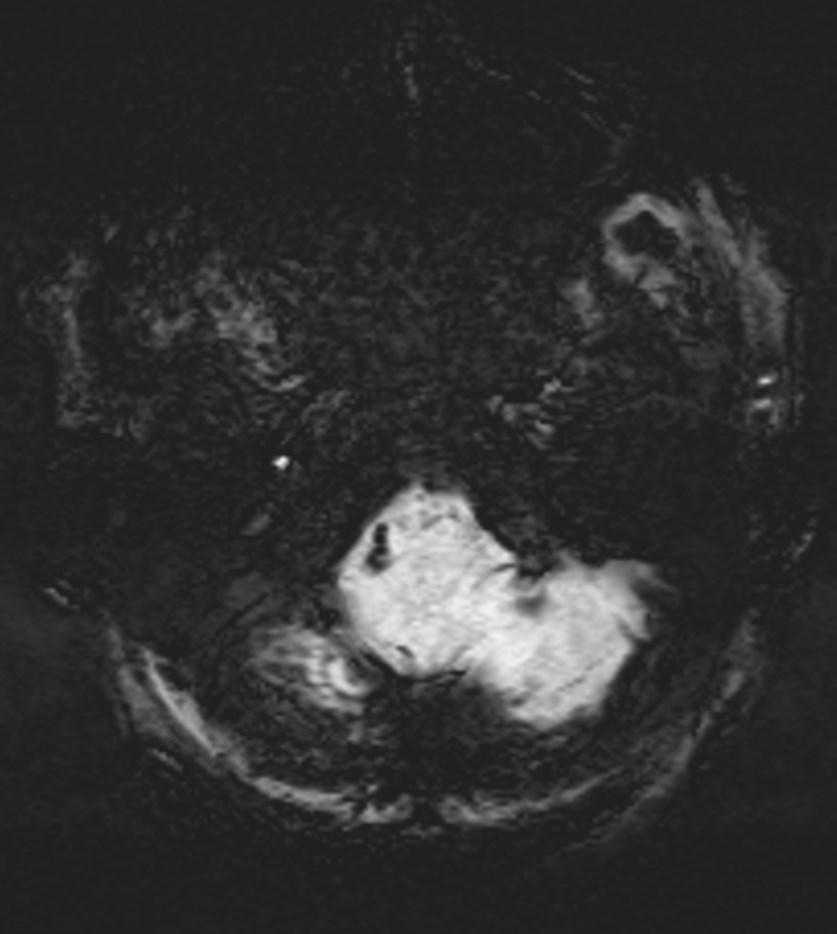

Right vertebral artery showing susceptibility sign on the SWI (arrows).